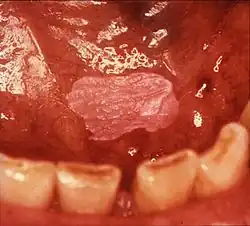

Erythroleukoplakia ("speckled leukoplakia"), left commissure. Biopsy showed mild epithelial dysplasia and candida infection. Antifungal medication may turn this type of lesion into a homogeneous leukoplakia (i.e. the red areas would disappear)

Erythroleukoplakia (also termed speckled leukoplakia, erythroleukoplasia or leukoerythroplasia) is a non-homogeneous lesion of mixed white (keratotic) and red (atrophic) color. Erythroplakia (erythroplasia) is an entirely red patch that cannot be attributed to any other cause. Erythroleukoplakia can therefore be considered a variant of either leukoplakia or erythroplakia since its appearance is midway between.[22] Erythroleukoplakia frequently occurs on the buccal mucosa in the commissural area (just inside the cheek at the corners of the mouth) as a mixed lesion of white nodular patches on an erythematous background,[22] although any part of the mouth may be affected. Erythroleukoplakia and erythroplakia have a higher risk of cancerous changes than homogeneous leukoplakia.[22]